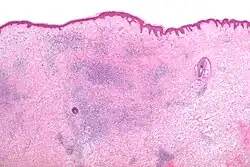

На микрофотографии показан клиновидный поверхностный кожный периваскулярный лимфоэозинофильный инфильтрат — гистоморфологическое появление укуса насекомого.

Гистоморфологические появления укусов насекомых, как правило, характеризуются появлением сосудистого инфильтрата, состоящего из лимфоцитов и эозинофилов.